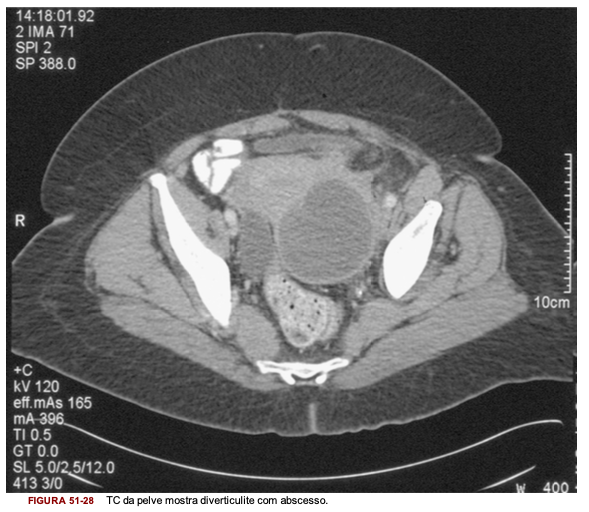

Qual o exame de imagem padrão ouro para o diagnóstico de diverticulite aguda?

O que esse exame fornece?

TC do abdome e pelve: mostra localização, extensão e gravidade da doença; além disso mostra alterações patológicas fora do cólon como um abscesso ou fístula colovesical

TC da pelve mostra diverticulite com abscesso